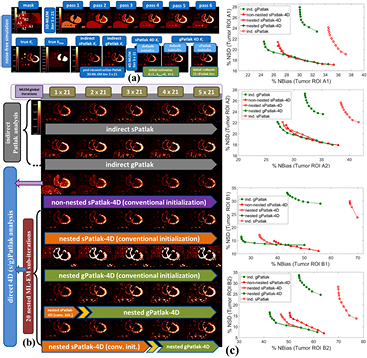

Then, a dynamic series of noise-free emission images were generated by assigning the modeled TACs to the respective regions of a voxelized XCAT human torso digital phantom at the time frames of the proposed protocol (figure 1). A total of six tumor regions were also added: three in the normal liver (A1, A2 and A3) and three in the right lung (B1, B2 and B3) background regions, with the members of each group having diameters in descending order of 15, 10, and 8 mm, respectively. Finally, tumor groups A and B were assigned the kinetics of liver and HCC metastatic tumors, respectively (table 1).

Later, analytic simulations were conducted by forward projecting the emission images with STIR (Thielemans et al 2012) using the Biograph mCT system geometry (Jakoby et al 2011). Then, the generated sinograms were attenuated, according to the XCAT attenuation factors, and scaled based on a factor accounting for the sensitivity of the mCT scanner and the time frame duration. Quantitative Poisson noise was then added. Finally, the generated noise-free and noisy dynamic PET projection data were all reconstructed in either 3D or 4D mode, using current and newly developed STIR ML-EM libraries to produce dynamic PET and Patlak parametric images, respectively. A diagram illustrating the design of the simulated study, along with examples of reconstructed Patlak images, is presented in figure 4.

Standard image High-resolution imageFor the evaluation of the 4D simulated data, ground truth kinetic parameters were known. Thus, the quantitative analysis was first conducted in terms of percentage (%) normalized bias (NBias × 100) and normalized standard deviation or noise (NSD × 100), where NBias and NSD were calculated over  simulated realizations, according to Karakatsanis et al (2013a), paragraph 4.2. Both metrics were extracted from four characteristic tumor regions (A1, A2, B1 and B2), as a function of the number of ML-EM iterations and plotted together to form noise-bias trade-off curves for each ROI and evaluated method. In addition, we assessed the mean target to background (TBR) and contrast to noise ratio (CNR) metrics for the same tumor regions after averaging over the 20 realizations, according to equations (18) and (19) below.

The noise-free dynamic PET SUV cardiac images in figure 5(a) (1st row) illustrate the variability introduced to each simulated lesion uptake and contrast during the first 45 min p.i. due to the modeled kinetics (table 1). The simulated dynamic PET images were produced from 3D ML-EM reconstruction (3 cycles of 21 iterations each) of dynamic cardiac data which were sampled according to our validated WB dynamic PET protocol (figure 1). Moreover, the reconstructed noise-free indirect and direct (s/g)Patlak Ki images in the 2nd row of figure 5(a) converged to higher lesion TBR contrast scores than any of the dynamic noise-free PET images for both ROI groups A and B. Therefore, in the absence of noise, Patlak may theoretically offer information beyond SUV and thus the complementary application of the two may enhance lesion detectability performance.

Figure 5. (a) Overview of noise-free Ki and kloss images and (b) noisy Ki images from simulated 4D PET data employing indirect and direct (s/g)Patlak methods. The orange and green bars denote sPatlak and gPatlak ML-EM global iterations respectively for the images directly above. In the last 2 rows, the yellow arrow position between the two bars designates at which iteration were the gPatlak estimates, on the right, initialized from the sPatlak estimates, on the left. (c) Quantitative Ki noise-bias trade-off analysis on four ROIs across 20 noise realizations. The red and green colors correspond to sPatlak and gPatlak methods, while the continuous and dotted delineations indicate direct and indirect methods, respectively. The triangle markers on red curves denote non-nested sPatlak method. Evaluations were conducted every 21 global ML-EM iterations, each consisting of 20 nested sub-iterations. Thus, gPatlak-4D was initialized after 3 × 21 = 63 sPatlak ML-EM iterations.

In noise-free conditions, indirect and direct methods are expected to match in performance, after convergence is attained. Indeed, no visually distinct difference was observed in the noise-free Ki images between the two method classes (figure 5(a)). In the presence of noise, however, the benefit in noise and resolution of properly initialized direct 4D versus indirect Patlak analysis is illustrated when visually comparing the noisy Ki simulated images (figures 4 and 5(b)), especially for the tumor lesions of B group in the right lung. Moreover, the noise-bias trade-off curves (figure 5(c)) clearly demonstrated, for all evaluated ROIs, the superiority of 4D sPatlak and properly initialized 4D gPatlak algorithms, relative to the respective indirect methods. In particular, we observed significantly reduced noise at matched bias (resolution) and vice versa for the direct 4D versus the indirect methods in all ROIs. Finally, the 4D methods converged to distinctly smaller bias values than indirect methods, thus suggesting reduced noise-induced bias compared to indirect Patlak.

A visual inspection of the ground truth Ki and kloss images and their comparison with the noise-free reconstructed Ki images in figure 5(a) (2nd row) suggests that, in general, the gPatlak indirect 3D and direct 4D methods were associated with more accurate Ki estimates than respective sPatlak methods. Furthermore, both noise-free and noisy gPatlak 4D reconstructions yielded relatively higher Ki TBR contrast scores, than respective sPatlak reconstruction, for tumor ROIs of group B, where a relatively higher degree of uptake reversibility (k4 = 0.012) was introduced in our simulations (table 1). Thus, our observations demonstrated the theoretical advantage of gPatlak over sPatlak algorithms, when evaluating regions exhibiting non-negligible uptake reversibility. However, the same results indicated lower Ki image noise for sPatlak versus the gPatlak 4 D methods. The respective noise-bias curves (figure 5(c)) confirmed the previous findings, as they revealed smaller bias at matched noise levels and higher noise at matched resolution (bias) for gPatlak 4D reconstruction methods.

3.1.4. Conventional versus nested Patlak 4D ML-EM and number of nested sub-iterations.

The expected gain in ML-EM convergence rate for the nested relative to the conventional, i.e. non-nested, 4D sPatlak implementations was illustrated qualitatively and quantitatively in figures 5(b) and (c) respectively. In particular, visual inspection of B1 and B2 lesions contrast as a function of the iteration cycles in simulated Ki images of figure 5(b) suggested a faster contrast recovery, and thus convergence rate, for the nested sPatlak Ki images. In addition, the respective noise-bias curves in figure 5(c) indicated smaller bias values at matched noise levels for the nested sPatlak 4D implementation.

The noise-free images in figure 5(a) demonstrate that the (s/g)Patlak 4D ML-EM algorithms converge in theory to the global optimal solution regardless of the initialization method. Thus, our findings indicated proper theoretical EM convergence properties for the implemented algorithms. In the presence of noise, however, the conventional method of initializing 4D ML-EM with Ki = 1, kloss = 0 and V = 1 parameter values, yielded correct EM convergence only in the case of 4D sPatlak method, as it can be conjectured by comparing 3rd and 4th row in figure 5(b). Nevertheless, as the Ki images of the last 2 rows in figure 5(b) illustrate, higher Ki lesion contrasts were attained with 4D gPatlak, compared to sPatlak (3rd row), after initializing the gPatlak 4D method with Ki and V estimates from the first 21 (5th row) or 3 × 21 = 63 (6th row) sPatlak iterations.

The importance of sPatlak-based initialization for gPatlak 4D algorithms was further demonstrated by the noted bias reduction as well as TBR and CNR score enhancements in figure 7 (1st column plots), when more sPatlak 4D global iterations were involved in the initialization of gPatlak 4D algorithm. However, after 3 cycles of 21 sPatlak ML-EM initial iterations, no additional benefit was observed for gPatlak 4D EM convergence rate. Thus, under noisy conditions, gPatlak 4D reconstruction may require a minimum number of sPatlak 4D iterations for its initialization, to ensure proper convergence and thus high quantification accuracy in Ki reconstructed images.

In figure 8, we present a set of indirect and direct (s/g)Patlak Ki WB images from a patient dataset at a 10–45 min p.i. scan time window. Moreover, the respective SUV WB PET image is also shown, as acquired at 60 min p.i. with the standard-of-care static PET protocol. The directly reconstructed (s/g)Patlak WB Ki images were estimated after five cycles of 21 ML-EM global iterations each. A nested 4D ML-EM implementation was employed at each bed position involving 20 sub-iterations. Furthermore, the first 3 out of the 5 ML-EM iteration cycles of the gPatlak 4D WB reconstruction consisted of sPatlak 4 D ML-EM iterations to initialize the 4th cycle of gPatlak ML-EM iterations (figure 9).

Figure 8. (1st row): clinical WB (s/g)Patlak Ki images, as estimated either indirectly or directly from the raw dynamic (10–45 min p.i) 18F-FDG PET data with 4D and indirect methods with patient arms at the bottom position to withstand longer scan duration. Also, the respective static SUV image obtained at 60 min p.i., after repositioning same patient with arms in the standard upper position (2nd and 3rd rows): TBR and CNR scores versus iterations for a range of (s/g)Patlak and SUV methods from a chest and a liver suspected tumor lesion ROIs.

Standard image High-resolution imageFigure 9. (1st row): clinical WB Ki images, estimated directly from the raw data of 6 WB passes with nested (s/g)Patlak 4D-MLEM methods. sPatlak 4D algorithm has been initialized with conventional method, while gPatlak 4D method utilizes the estimates of previous sPatlak 4D method after 3 cycles of 21 ML-EM iterations. All methods employ 20 nested sub-iterations. (2nd and 3rd rows): clinical TBR and CNR evaluation on 2 selected chest ROIs drawn from patient WB Ki images as a function of the initialization scheme and number of nested sub-iterations employed by the proposed (s/g)Patlak 4D WB reconstruction methods.

The spatial noise levels visually observed in the background regions of the selected liver and chest target ROIs of WB 4D (s/g)Patlak Ki clinical images of figure 8 were comparable to the respective static SUV image noise. This is also evident by comparing the TBR and CNR scores of respective clinical Ki and SUV images for both evaluated ROIs in the same figure. In particular, the superiority of Ki imaging, relative to SUV, in terms of TBR contrast is also retained to nearly the same or higher degree in terms of CNR score. As CNR is derived from TBR after normalizing the latter with spatial noise in the target background, the previous observation suggest similar or lower quantitative levels of spatial noise between direct 4D Ki and SUV clinical images, at least for the two evaluated ROIs. Thus, our results demonstrate the clinical feasibility of 4D WB Patlak Ki methods, when applied on a streamlined 6-pass WB PET protocol. In addition, the superior TBR and CNR 4D Ki scores, relative to SUV, on the two identified ROIs indicate potential enhancement of tumor detectability performance, when complementing the currently established in clinic WB SUV imaging protocols with the proposed direct 4 D WB (s/g)Patlak methods.

The images in figure 8 illustrated the lower noise of direct 4D relative to indirect Patlak methods. Moreover, the quantitative plots in figure 8 demonstrated the superior TBR and CNR performance for all 4D Patlak methods, compared to the respective indirect methods, particularly for the chest ROI. The improvement was more evident in terms of the CNR metric, owing to the lower noise levels observed in the 4D reconstructions versus indirect Patlak analysis. Our clinical findings confirmed the simulation results and can be explained by the more efficient utilization of the acquired data with 4D Patlak algorithms. Finally, the quantitative TBR and CNR analysis suggested that the gain observed when switching from indirect to direct 4D Patlak methods is relatively larger than the respective gain between standard and generalized Patlak models.

3.2.3. sPatlak versus gPatlak 4D WB clinical imaging.

Our clinical validation results in figure 8 demonstrated the superior TBR lesion contrast scores for nested gPatlak 4D Ki images, both via the qualitative inspection of the respective patient WB Ki images as well as through the quantitative TBR analysis in both evaluated ROIs. Moreover, despite the higher noise levels observed in gPatlak Ki images, relative to sPatlak, the highest clinical ROI CNR scores were systematically observed for the former. Besides, the clinical TBR and CNR score differences between the two 4D Patlak methods were not as significant as the respective differences between (i) indirect sPatlak and gPatlak or (ii) direct versus indirect Patlak methods. In other words, the differences between the two Patlak models were less significant in the 4D framework.

3.2.4. Clinical impact of number of nested sub-iterations and gPatlak initialization.

The series of WB Ki images in figure 9 illustrate the convergence of sPatlak and gPatlak 4D methods, when applied to the same patient dataset and after being initialized with the proposed schemes. The two 4D algorithms converged to different but similar sPatlak and gPatlak solutions in the last two cycles of 21 iterations.

Moreover, the TBR and CNR plots describe the quantitative effect on 2 chest ROIs of the number of nested ML-EM sub-iterations as well as that of sPatlak-based initialization for gPatlak 4D algorithm. In particular, the plots of the 2nd row suggested superior TBR and CNR performance for both ROIs in clinical gPatlak-4D Ki images, when at least 3 × 21 ML-EM sPatlak iterations are employed for its initialization. Any higher number of iterations only resulted in negligible convergence acceleration. Furthermore, the TBR and CNR scores of the 3rd row suggested a minimum number of 20 nested ML-EM sub-iterations to sufficiently accelerate convergence without increasing noise in the Ki images.